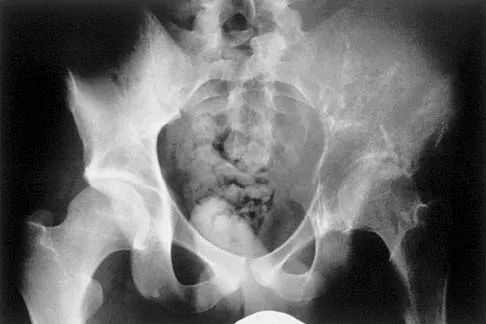

A 25-year-old man has had an insidious onset of left hip pain over the past 11 months. A radiograph, coronal MRI scan, and histopathologic specimens are seen in Figures 2a through 2d. What is the most likely diagnosis?

Explanation

Ewing's sarcoma is the second most common primary sarcoma of bone in children and young adults. It is a malignant round cell tumor with uncertain histogenesis. Sheets of uniform small round blue cells with a high nuclear-to-cytoplasm ratio and the absence of osteoid formation differentiate this histologic diagnosis from the other conditions. Immunohistochemical staining and molecular diagnostic studies are useful to verify the diagnosis.